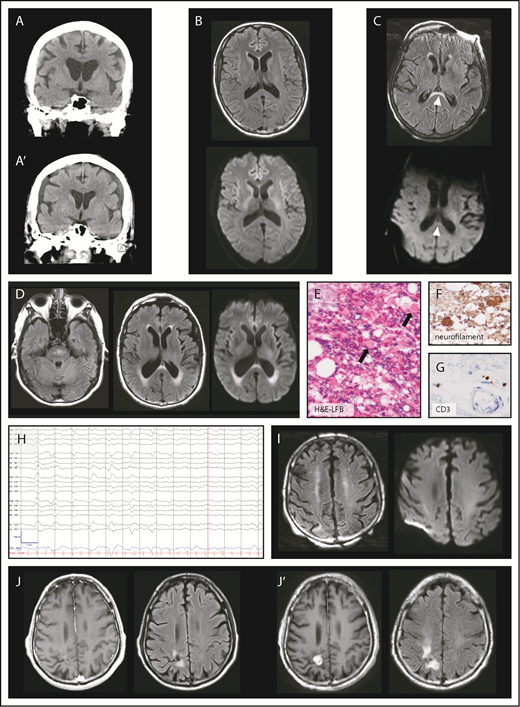

Twenty-one patients underwent neuroimaging with cranial CT as part of their workup for CAR T-cell therapy-induced neurotoxicity, which revealed normal findings in 20 patients (20/21, 95%). One patient with grade 4 neurotoxicity had a normal head CT scan when neurologic symptoms started (Figure 2A) but developed subdural hematoma 13 days later (Figure 2A′). The patient became obtunded with no history of falls between the 2 CT scans.

Brain imaging and electroencephalography during neurotoxicity. (A) Normal CT of the brain at onset of neurotoxicity (top) and subdural hematoma 13 days later (A′). (B) Axial MRI of the brain with normal FLAIR (top) and diffusion-weighted imaging (DWI, bottom) sequences during acute neurotoxicity. (C) Axial FLAIR image (top) in a patient with severe neurotoxicity demonstrating a lesion (arrowheads) of the splenium of the corpus callosum partly characterized by restricted diffusion on DWI sequences (bottom). (D) Axial FLAIR hyperintensities of the brainstem (left) and the periventricular white matter (middle) were found in a patient with left-sided visual field deficit who presented 30 days after CAR T-cell infusion. Periventricular lesions were characterized by restricted diffusion on DWI sequences (right). Luxol fast blue (LFB) with hematoxylin and eosin (H&E) (E), neurofilament (F), and CD3 (G) stains of a tissue specimen taken from the periventricular lesion in panel D shows axonal injury of the optic radiation (original magnification, ×400). H&E-LFB demonstrates vacuolization and axonal spheroid formation (arrows). Immunohistochemical staining for neurofilament shows enlarged circular brown material consistent with axonal spheroids within white matter, a finding characteristic for Wallerian degeneration. Immunohistochemical staining for CD3 highlights T cells in scant numbers, primarily present in perivascular regions. (H) Electroencephalography of a patient who developed myoclonus and confusion 10 days after CAR T-cell infusion. Low-frequency blunted generalized periodic discharges admixed with rhythmicity on an alternating background between δ and θ slowing are displayed. The snapshot is seen in a longitudinal bipolar montage (left-right-left-right-midline): sensitivity, 7 μV/mm; time base, 30 mm/s; low-frequency filter, 1 Hz; high-frequency filter, 70 Hz; and notch, 60 Hz. (I, left) Axial FLAIR image in a patient with confusion after rituximab-lenalidomide infusion shows bilateral curvilinear hyperintensities in the juxtacortical frontoparietal white matter without restricted diffusion on DWI sequences (right). (J) Axial T1-weighted MRI postcontrast and FLAIR images demonstrate a radiosurgery lesion pre-CAR T-cell infusion (left) and evidence of radiation necrosis with contrast enhancement after CAR T-cell infusion (J′).

Ten patients consisting of 2 low- and 8 high-grade neurotoxicity patients had cranial MRI performed during acute symptoms. Imaging was unrevealing in patients with low-grade neurotoxicity and in 6 patients with high-grade neurotoxicity (8/10, 80%) (Figure 2B). One patient had new periventricular hyperintensities and a lesion anterior to the splenium of the corpus callosum on T2-weighted fluid attenuation inversion recovery (FLAIR) imaging with associated restricted diffusion (Figure 2C). One patient had mild neurotoxicity that completely resolved, but 30 days after infusion presented with visual field deficit rapidly progressing to bilateral blindness and extremity weakness with upper motor neuron signs. MRI showed patchy T2-weighted FLAIR hyperintensities without corresponding restricted diffusion within the pons and hyperintensities with restricted diffusion within the periventricular white matter along the lateral ventricles and the splenium (Figure 2D). The patient died 10 weeks after CAR T-cell infusion; pathology showed axonal injury mostly affecting bilateral optic radiations (Figure 2E-G). However, this clinical phenotype was attributed to fludarabine-induced leukoencephalopathy and not interpreted as a direct consequence of CAR T cells.

EEG during acute neurologic symptoms was performed on 18 patients, including 6 with low-grade neurotoxicity and 12 with high-grade neurotoxicity. All 18 patients were found to have diffuse or frontal background slowing in the θ and δ frequency ranges. Periodic or rhythmic patterns within the ictal-interictal continuum were seen in 3 of 6 low-grade neurotoxicity patients (50%) and 11 of 12 high-grade neurotoxicity patients (92%) (Figure 2H). The following ictal-interictal patterns were encountered and in part occurred concurrently: generalized period discharges (GPD; 9/18 patients, 50%); generalized rhythmic δ activity (8/18, 44%); frontal intermittent rhythmic δ activity (2/18, 11%); bilateral independent periodic discharges (2/18, 11%); and stimulus-induced rhythmic, periodic, or ictal discharges (2/18, 11%). Burst suppression was induced in 3 patients with high-grade neurotoxicity, and status epilepticus was found in 2 high-grade neurotoxicity patients. Of note, some clinical events of involuntary rhythmic movements remained without EEG correlate.

Two patients had neurotoxicity after CAR T-cell infusion which completely resolved, however, they presented more than 30 days after CAR T-cell infusion with new neurologic symptoms and new imaging findings. First, 1 patient with prior high-grade neurotoxicity had lymphoma recurrence 4 months after CAR T-cell therapy, and salvage therapy with rituximab-lenalidomide was initiated. The patient subsequently developed confusion and myoclonus; MRI of the brain revealed frontoparietal FLAIR hyperintensities (Figure 2I). Second, 1 patient with a medical history of γ knife radiosurgery 6 months before CAR T-cell infusion (Figure 2J) and prior low-grade neurotoxicity presented with left-sided weakness 1 month after infusion, and was found to have exacerbation of radiation necrosis (Figure 2J′). Whereas there is evidence that symptoms of the first patients may be associated with CAR T cells,20 the latter case of radiation necrosis was believed to be an event occurring independently from CAR T cells.